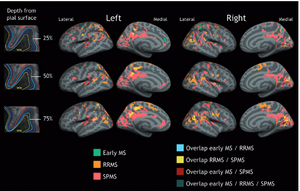

- 3.45 A Gradient in Cortical Pathology in Multiple Sclerosis by in vivo Quantitative 7 T Imaging